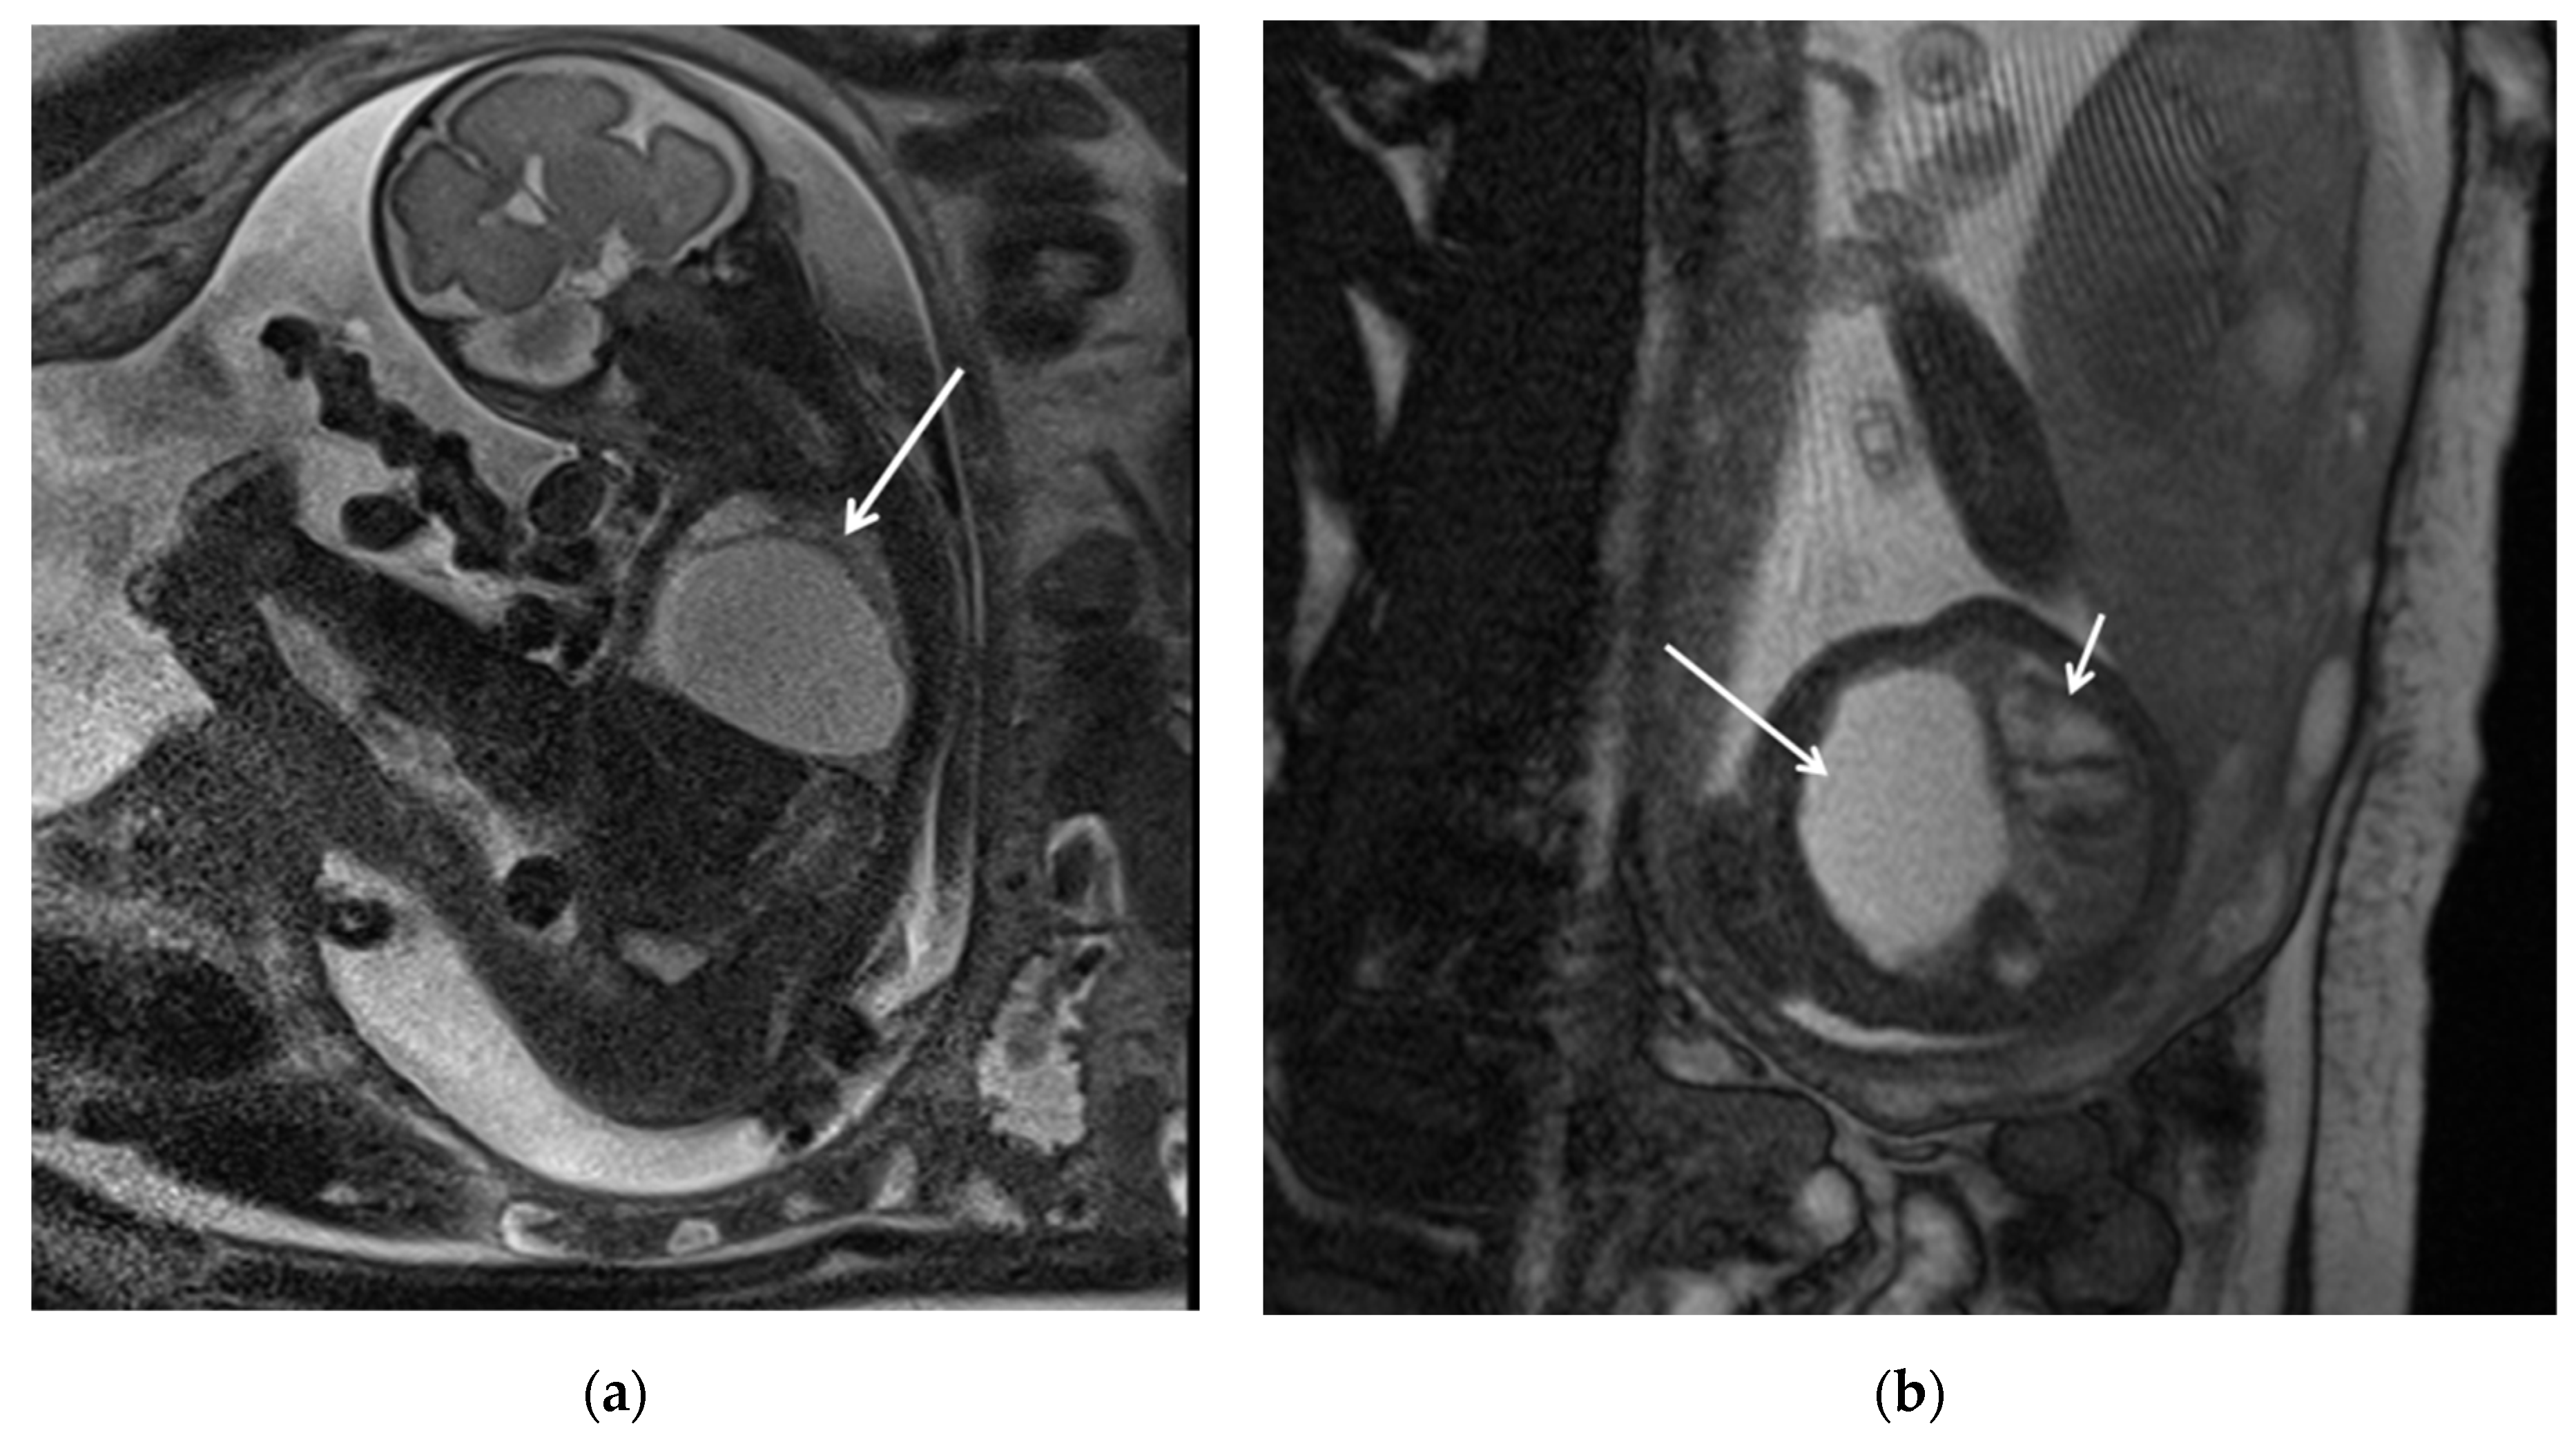

Figure 1. CPAM type I. HASTE oblique sagittal (a) and True FISP (b) MRI scans taken at 28 weeks of gestation reveal a large fluid-filled mass with bright T2 signal in the right chest (arrows). This abnormality results in a shift of the heart toward the left side of the mediastinum.